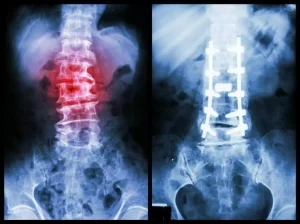

پیچهای پدیکل (Pedicle Screws) ابزاری نوآورانه در جراحی ستون فقرات هستند که طی چند دهه اخیر با هدف تقویت و

فیوژن مهرهها در ستون فقرات به معنای اتصال مهرهها به یکدیگر است. در این نوع جراحی، ممکن است دو یا